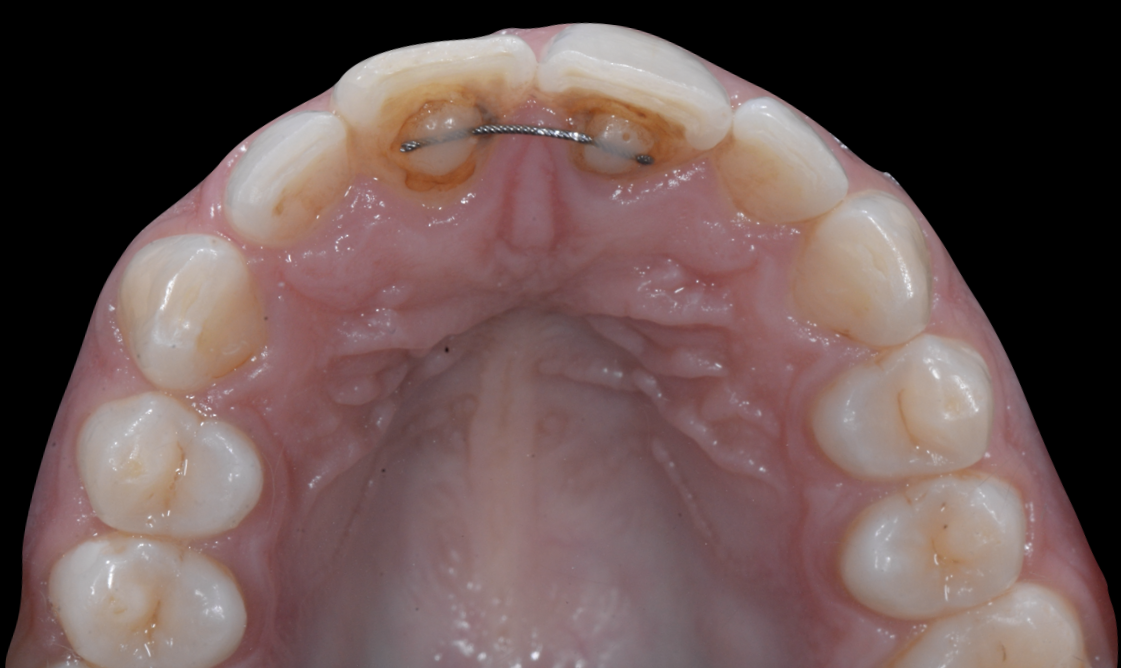

De manière consensuelle, ce syndrome définit des déplacements dentaires aberrants, inattendus, inexpliqués ou excessifs, concernant des dents contenues par un fil de contention post orthodontique intact (Charavet et al. 2022). Il s’agit d’un processus chronique, évolutif, généralement asymptomatique, aboutissant à une nouvelle malocclusion qui ne résulte pas d’une récidive ou d’un processus physiologique d’adaptation des complexes dento-parodontaux (Figures 1). Ses causes seraient multiples et restent à éclaircir.

Figures 1 : syndrome du fil détecté 4 ans après la pose de la contention collée mandibulaire. Les incisives encore contenues se sont versées, soit en vestibulaire, soit en lingual. Il ne s’agit pas d’une récidive.

Figures 2 : syndrome du fil maxillaire : version palatine de la 11 et version vestibulaire de la 21 (Documents : Pr Charavet Carole)